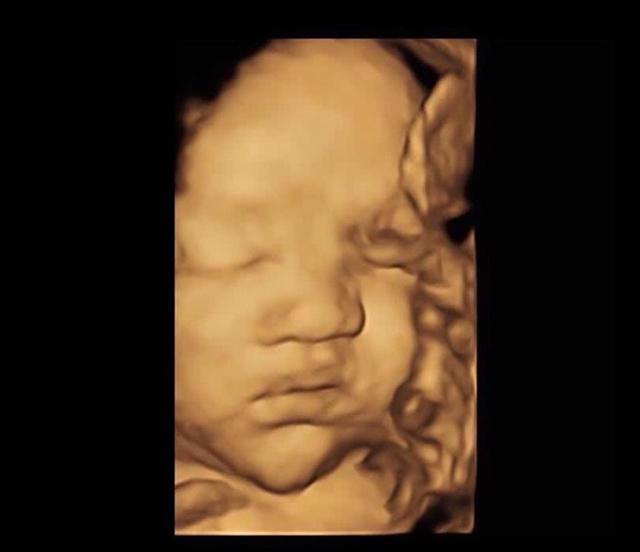

孕婦產檢做「四維」胎兒變「數學天才」

鄰居小夏自從懷孕後十分小心謹慎,每一次產檢都提前準備,生怕怠慢了肚子裡的小傢伙,不過這次產檢也讓小夏有了新的發現。

小夏這次去醫院做四維(超音波成像),通過屏幕顯示出來肚子裡的小傢伙正在擺弄著手勢,小夏仔細看了看,好像是數字「4」,她立刻拿出以前做四維的照片給醫生看。

原來小夏每一次做四維她都把胎兒在子宮裡的情況照下來,加上這次正好四次,而每次四維顯示出來的胎兒都在子宮裡擺出不同姿勢和手勢,但是連在一起就非常像小朋友「數數」,因為四次四維圖象連在一起胎兒的手勢正好是數字「1234」。